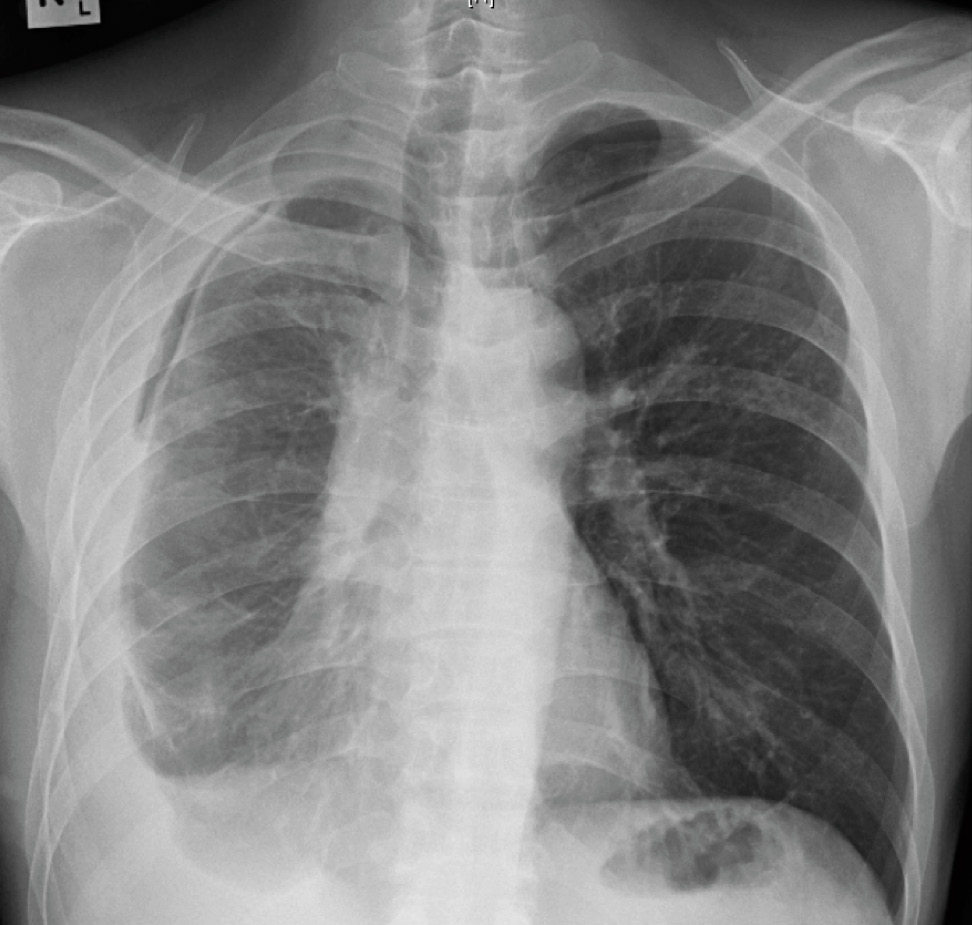

He felt clinically better after starting the anti-tuberculosis therapy, with no further fever nor shortness of breath (except on exertion), and had also started to gain weight. The pleural fluid culture was positive for Mycobacterium tuberculosis complex which was sensitive to all drugs. During the routine follow-up visit after completing 2 months of therapy, however, the chest X-ray was grossly abnormal.

Chest X-ray 2 months after starting anti-tuberculosis therapy, showing a massive right pleural effusion.